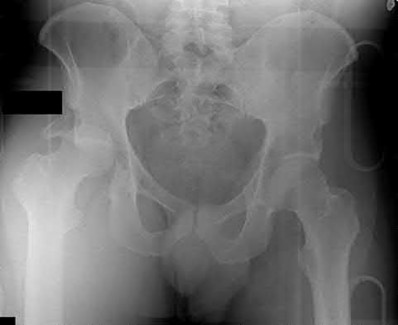

3. # Which of the following is not an appropriate implant for treatment of the fracture seen in Figure A?

5. Sliding hip screw Corrent answer: 5

The image shows a reverse obliquity intertrochanteric hip fracture.

According to the referenced article by Haidukewych et al, unstable peritrochanteric hip fractures have a worse outcome (failed in 9/16 cases) if treated with a sliding hip screw. Two additional factors that were found to have a strong correlation with postoperative failure (nonunion, loss of reduction) were poor reduction and poor implant placement. In this study, fixed angle devices were superior. Intramedullary fixation has the added advantage of a shorter lever arm and less potential for fracture collapse and limb shortening.

The IMN also acts as a medial buttress.

According to Sanders et al, the dynamic condylar screw (DCS) can also be used in subtrochanteric models, but should not be used if extensive comminution is seen, as they reported a high failure rate with DCS in these fractures if highly comminuted. They report a 77% overall union rate with this device.